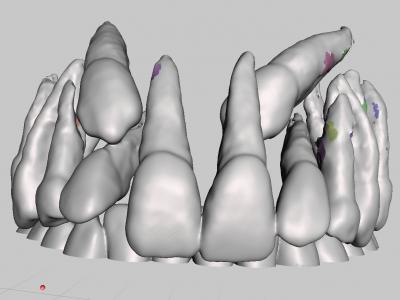

- Etape de seuillage : sélection d'un intervalle de densité (Unités Hounsfield) : par exemple 470 à 3000 pour os + dents, ou 1500 à 3000 pour les dents seules (situation qui nous intéressera dans ce cas).

Il est malheureusement quasiment impossible de sélectionner uniquement les dents sans avoir des éléments osseux. Il faut trouver le bon équilibre entre des surfaces dentaires et radiculaires nettes et le moins d'éléments osseux adjacents. Ces éléments osseux seront ensuite nettoyés dans Meshmixer.

Plusieurs itérations sont parfois nécessaires afin de trouver le meilleur équilibre.